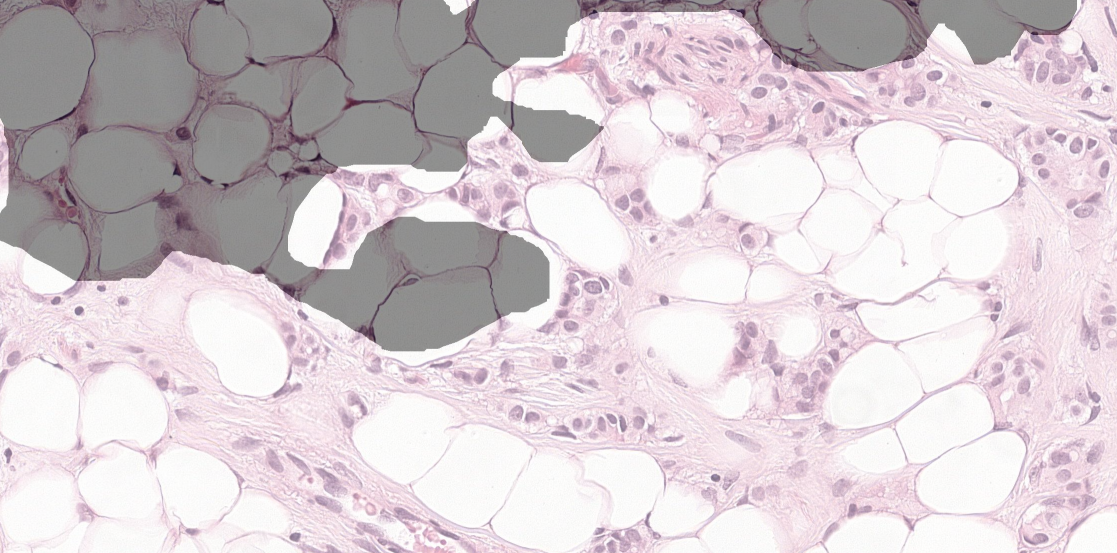

Given a gigapixel pathology image (slide111Each slide contains human lymph node tissue stained with hematoxylin and eosin (H&E), and is scanned at the most common high magnification in a microscope, “40X”. We also experimented with 2- and 4-times down-sampled patches (“20X” and “10X”).), the goal is to classify if the image contains tumor and localize the tumors for a pathologist’s review. This use case and the difficulty of pixel-accurate annotation (Fig. 3) renders detection and localization more important than pixel-level segmentation. Because of the large size of the slide and the limited number of slides (), we train models using smaller image patches extracted from the slide (Fig. 1). Similarly, we perform inference over patches in a sliding window across the slide, generating a tumor probability heatmap. For each slide, we report the maximum value in the heatmap as the slide-level tumor prediction.

Datasets Our work utilizes the Camelyon16 dataset [1], which contains 400 slides: 270 slides with pixel-level annotations, and 130 unlabeled slides as a test set.333The test slides labels were released recently as part of the training dataset for Camelyon17. We used these labels for evaluation, but not for parameter tuning. We split the 270 slides into train and validation sets (Appendix) for hyperparameter tuning. Typically only a small portion of a slide contains biological tissue of interest, with background and fat comprising the remainder (e.g., Fig. 3). To reduce computation, we removed background patches (gray value [12]), and verified visually that lymph node tissue was not discarded.

We also experimented with a multi-scale approach inspired by pathologists’ workflow of examining a slide at multiple magnifications to get context. However, we find no performance benefit in combining 40X with an additional input at lower magnification (Fig. 3). However, these combinations output smoother heatmaps (Fig. 4), likely because of translational invariance of the CNN and overlap in adjacent patches. These visual improvements can be deceptive: some of the speckles in the 40X models reveal small non-tumor regions surrounded by tumor.

Figures 1 and 3 highlight the variability in the images. Although the current leading approaches report improvements from color normalization, our experiments revealed no benefit (Appendix). This could be explained by our extensive data augmentations causing our models to learn color-invariant features.

0.A.3 Image Color Normalization

As can be seen in Fig. 1 & 3, the (H&E) stained tissue vary significantly in color. These variations arise from differences in the underlying biological tissue, physical and chemical preparation of the slide, and scanner adjustments. Because reducing these variations have improved performances in other automated detection systems [4, 13], we experimented with a similar color normalizing approach. However, we have not found this normalization to improve performance, and thus we detail our approach for reference only. This lack of improvement likely stems from our extensive color perturbations encouraging our models to learn color-insensitive features, and thus the color normalization was unnecessary.